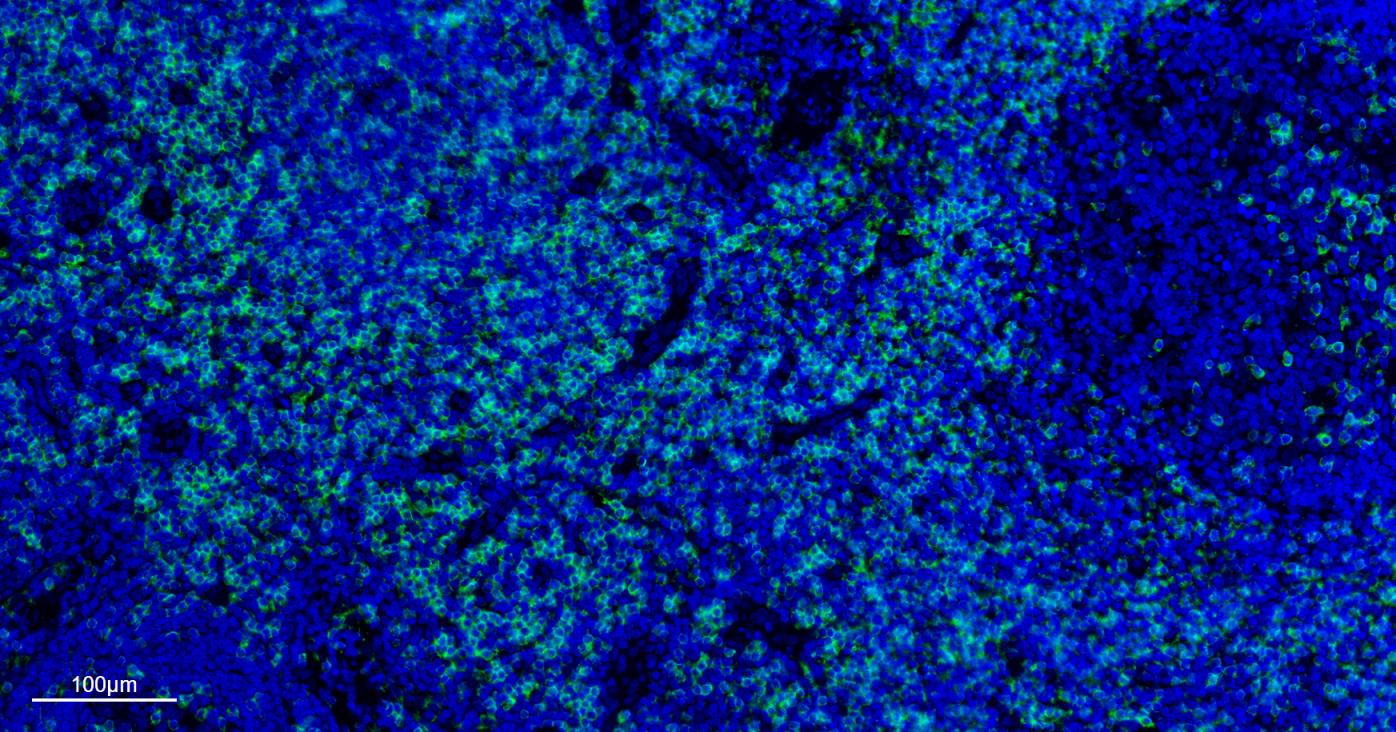

| IF | Human | 1:100-500 | |

| mIHC | Human | 1:100-500 |